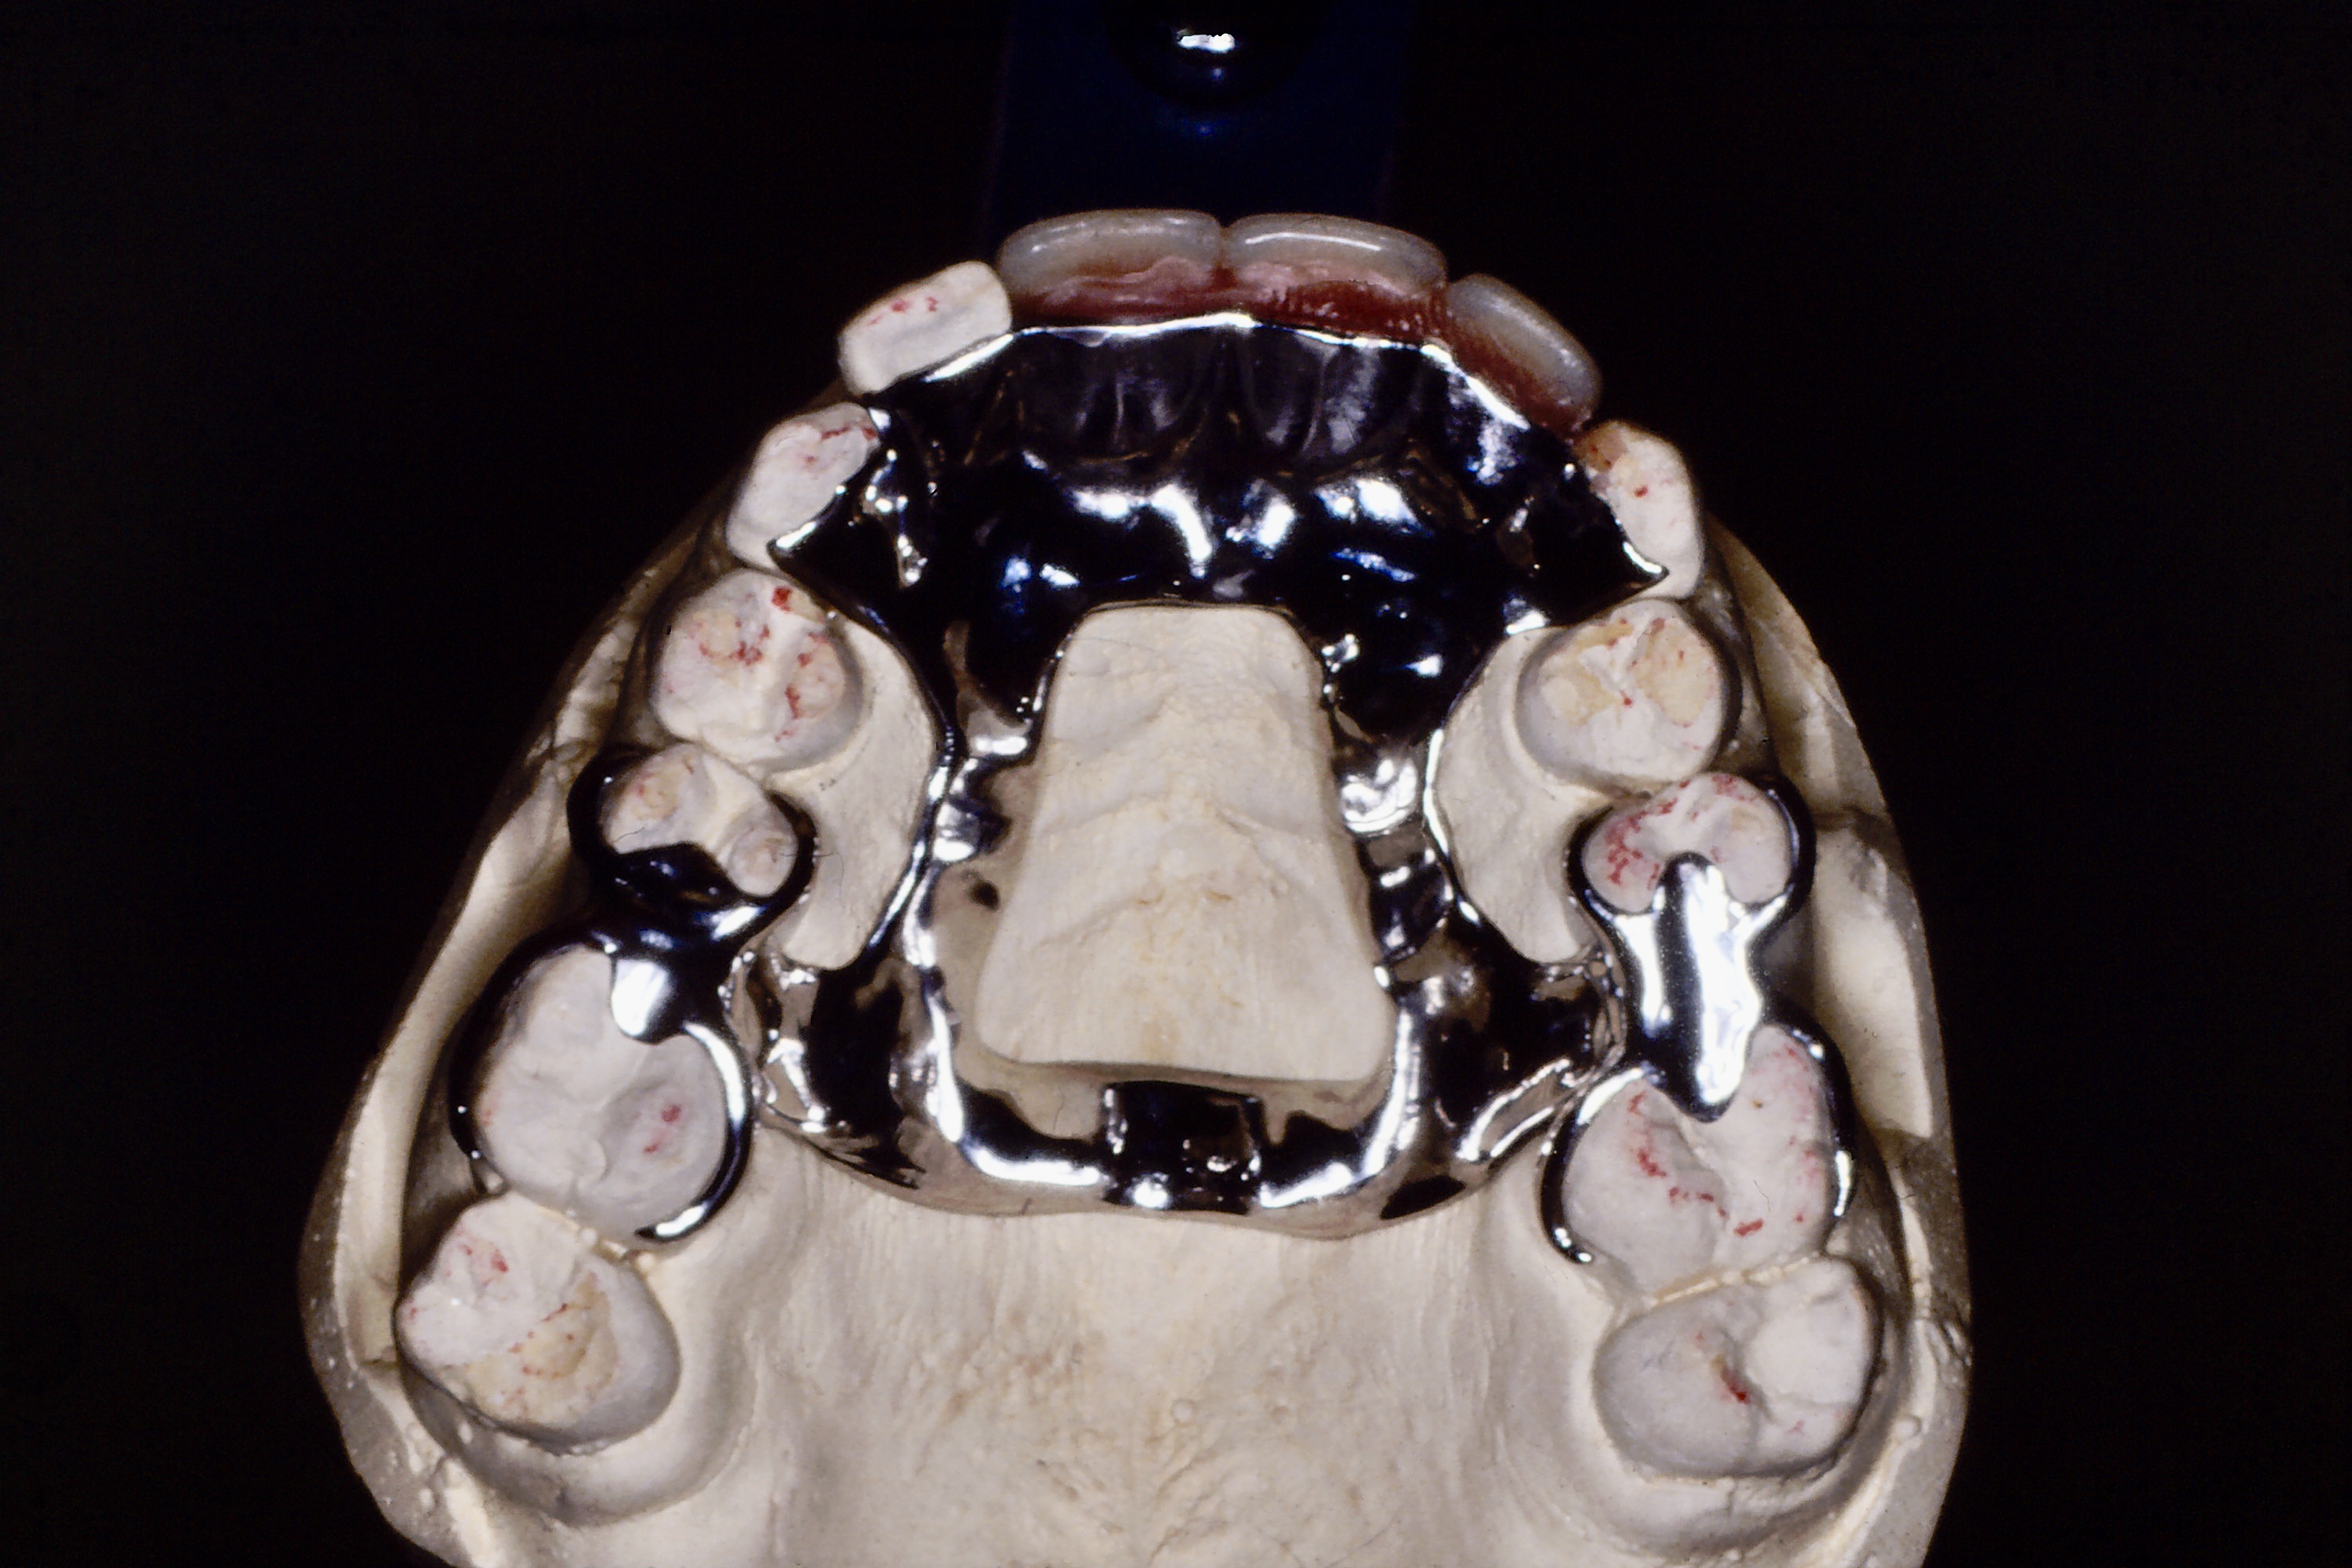

אלו הן תותבות נשלפות המשחזרות חוסר חלקי של שיניים ונסמכות על ידי ווים או אמצעי אחיזה אחרים על שיניים או כתרים הקיימים בפה. תותבות מעין אלו עשויות בדרך כלל מיציקה של שלד מתכתי , כרום קובלט,או מפלסטיק - אקריל כשחזור זמני, עליו נטועות שיני פלסטיק המשחזרות את השיניים החסרות בעמדה גודל וצבע זהים לשיניים הקיימות